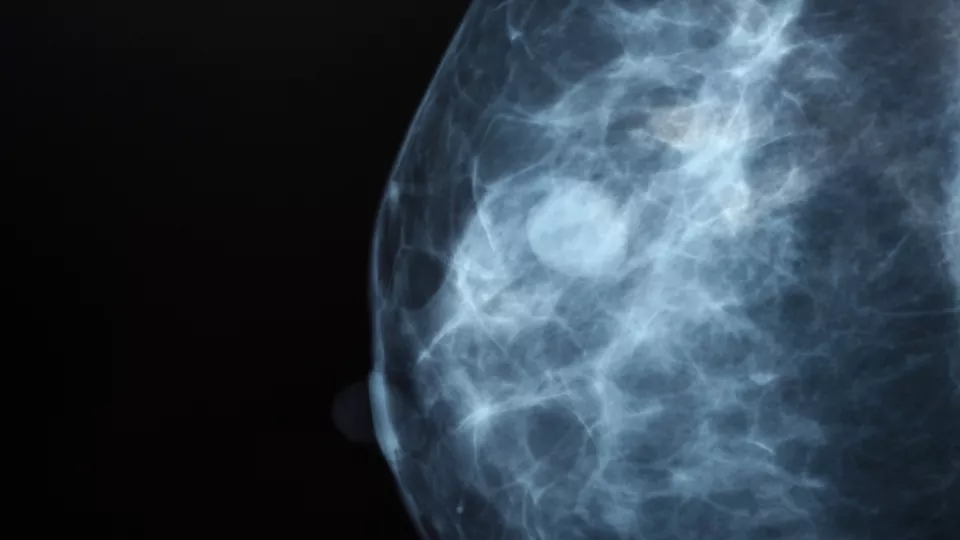

Breast screening image, photo: iStock

Pre-cancerous lesions, known as in situ cancers, were also more likely to be detected with AI – 51 per cent more such cases were found (68 people compared with 45). Photo: iStock